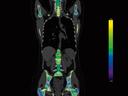

The question is: What makes True Dual Energy stand out? Look for these three criteria: crisp images with the option for even sharper contrast and significant artifact reduction; no extra dose in either Single Source or Dual Source Dual Energy scans, and a broad applicability for virtually all clinical questions and patients.

Discover Dual Energy (DE) spectral imaging. It’s the difference between images and answers. Visualization and characterization. Qualification and quantification. Built into all of our CT scanners, it delivers powerful performance, incredible versatility for your entire patient population, and exceptional ease-of-use – all while integrating seamlessly with your current workflow.